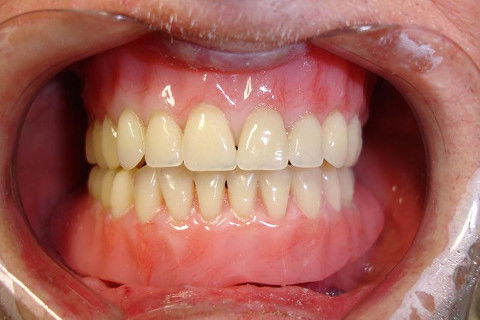

Vista frontal da prótese total superior e overdenture inferior.

Instalação final das próteses.